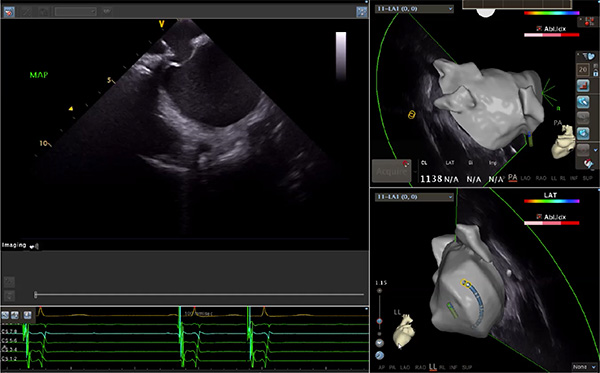

超聲心動(dòng)圖技術(shù)包括常規(guī)經(jīng)胸超聲(TTE)、經(jīng)食管超聲(TEE)、心腔內(nèi)超聲(ICE)、超聲聲學(xué)造影(MCE)、三維超聲心動(dòng)圖等,ICE是一種新興技術(shù)——將微型的換能器安裝在心導(dǎo)管的尖端,經(jīng)由外周血管輸送至心腔內(nèi)部,換能器發(fā)射聲波,對(duì)心臟及其鄰近組織進(jìn)行實(shí)時(shí)高質(zhì)量成像和(或)血流動(dòng)力學(xué)測(cè)定的超聲成像技術(shù)。基于不同的技術(shù)原理,心腔內(nèi)超聲導(dǎo)管被分為兩類:機(jī)械旋轉(zhuǎn)式超聲導(dǎo)管和相控陣超聲導(dǎo)管。目前,臨床上主要應(yīng)用的是相控陣超聲導(dǎo)管,ICE成像通過術(shù)者旋轉(zhuǎn)導(dǎo)管及操縱導(dǎo)管手柄上的兩個(gè)旋鈕來(lái)完成。

ICE門檻高、集成了超聲和圖像處理最前端的技術(shù),是當(dāng)前內(nèi)窺超聲方向最挑戰(zhàn)的領(lǐng)域。不同于傳統(tǒng)接觸式三維重建方法會(huì)產(chǎn)生假腔,影響術(shù)者對(duì)靶點(diǎn)或結(jié)構(gòu)的判斷,心腔內(nèi)超聲(ICE)可直接顯示心臟結(jié)構(gòu),有助于理解心臟內(nèi)各部位之間的解剖關(guān)系,不僅具有實(shí)時(shí)成像、并發(fā)癥監(jiān)測(cè)以及良好的耐受性,同時(shí)以股靜脈入路,無(wú)需全麻或深度鎮(zhèn)靜,日益成為心臟介入手術(shù)中重要輔助工具,被譽(yù)為心臟介入醫(yī)生的“黃金眼”。心腔內(nèi)超聲可用于多種心臟介入手術(shù),潛在患者群體龐大,動(dòng)脈網(wǎng)測(cè)算我國(guó)心腔內(nèi)超聲導(dǎo)管市場(chǎng)空間或?qū)⒊?00億元,具有廣闊前景。

隨著心腔內(nèi)超聲的應(yīng)用更廣,性能也在逐漸優(yōu)化,已從二維成像轉(zhuǎn)變?yōu)?strong>三維成像,極大增強(qiáng)了引導(dǎo)及可視化能力。二維心腔內(nèi)超聲支持雙平面或三平面成像,可顯示兩個(gè)或三個(gè)不同的平面視圖,但醫(yī)生需將這些圖像在腦海中重新構(gòu)建為三維解剖結(jié)構(gòu)。三維心腔內(nèi)超聲則可直接呈現(xiàn)三維解剖結(jié)構(gòu)圖,便于醫(yī)生更輕松地開展手術(shù)。按照產(chǎn)品發(fā)展方向,預(yù)計(jì)心腔內(nèi)超聲還將向更清晰、精準(zhǔn)、多功能等方向發(fā)展。